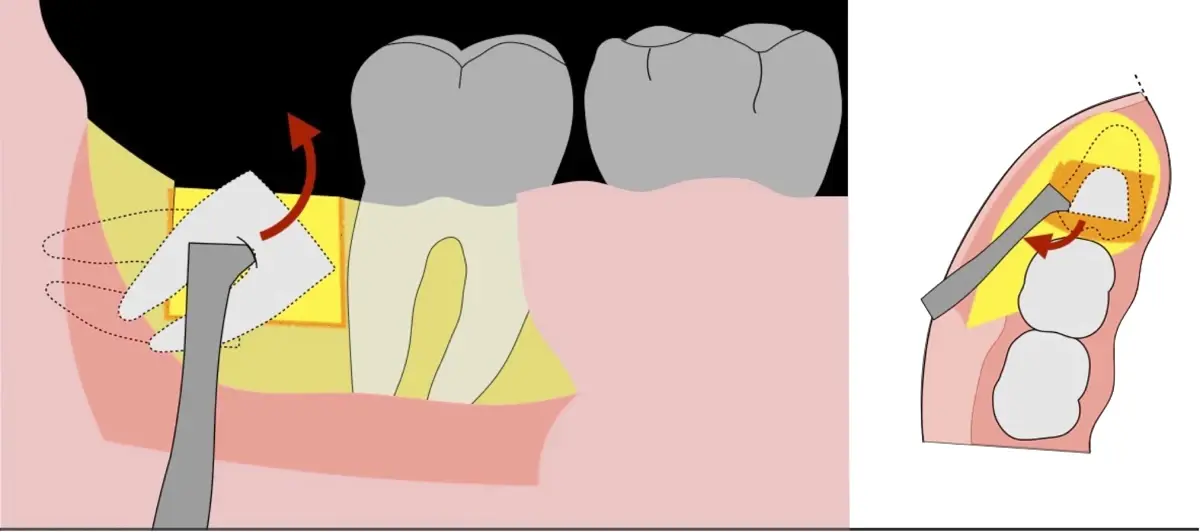

Es imprescindible conocer la ubicación de la tercera molar. Se puede emplear, adicionalmente a la evaluación clínica, herramientas radiográficas (panorámica y periapical) y tomográficas (Cone beam) para determinar la posición, grado de retención y proximidad a estructuras vecinas de riesgo como el nervio dentario inferior y así evitar lesiones (Figura 1).